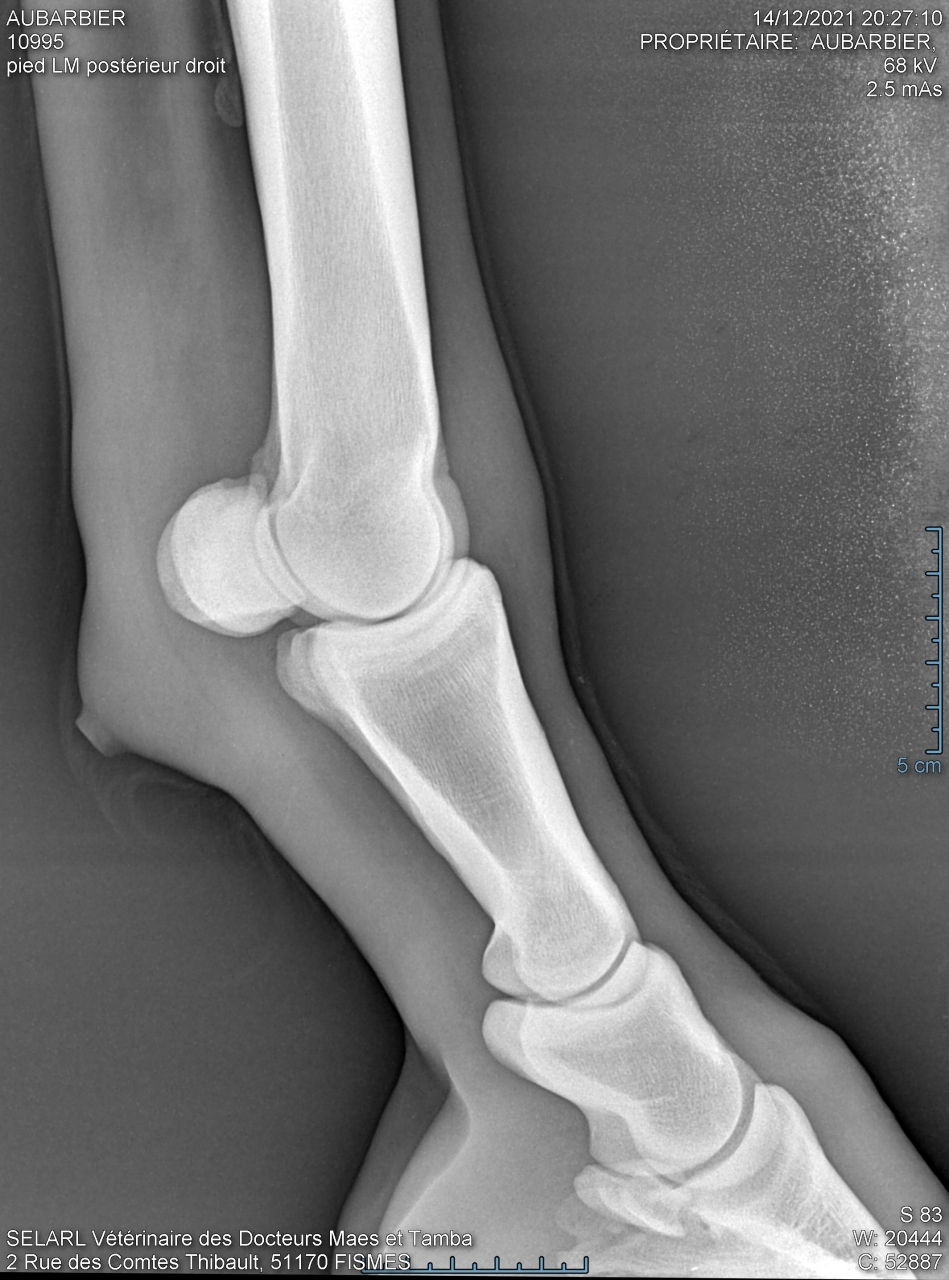

| Dire merci | hello je fais appel à cette commu pour m'aider à comprendre des radios du postérieur de ma jument pour vous situer : je l'ai acheté le 10 novembre de cette année, je l'ai monté 10 fois en tout et à la 10ème séance (13 jours après l'achat) elle s'est mise à ne plus poser le pied par terre (on sautait et elle a boité dès que je suis descendue). Je précise qu'il n'y a eu aucun choc, ni chute. Depuis elle est au box et on a tout essayé chaud, froid, argile, avec fers, sans fers… Tout son postérieur n'est ni gonflé, ni chaud, ni douloureux, et n'a pas mal au test de la pince sur la sol mais impossible de poser son pied ni de lever les autres sinon elle se laisse tomber… La véto a fait des radios que je vais mettre en pièces jointes mais n'a pas rendu de verdict car elle a voulu une relecture par la clinique de Charlevilles Est ce que quelqu'un pourrait m'aider please ? |

| Dire merci | Il n'est pas sur du tout que la pathologie qui fasse boîter votre jument se voit aux radios. Parfois il faut un scanner en plus. Cela peut être tout et n'importe quoi. D'ailleurs la boiterie peut venir d'un autre endroit que l'endroit radiographié. Sans choc/accident évident, vous pouvez être partie pour une batterie d'examens. Avez-vous fait une visite d'achat ? Y avait -il déjà des clichés ? Vous a t-on parlé d'une fragilité particulière ? D'antécédents ? ... |

| Dire merci | Moi je vois un possible chemin d’abcès Qu’a dit la clinique ? |